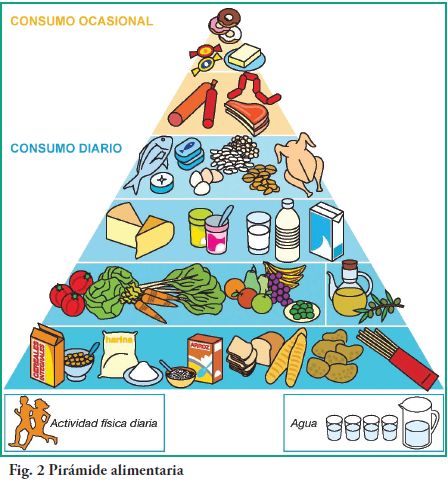

conjuntivo. Su alteración en pacientes diabéticos ocasiona modificaciones en el tejido conjuntivo que generan retardo en la cicatrización de heridas, menor formación ósea y disminución del crecimiento (12). El niño con diabetes tipo 1 tiene las mismas necesidades nutricionales que sus pares sin diabetes. Requiere un aporte calórico acorde a su edad para lograr un adecuado crecimiento y desarrollo (13).

La dieta equilibrada desde el punto de vista nutricional desempeña un papel primordial en el crecimiento y desarrollo normal de niños y adolescentes.

Los padres de niños y adolescentes, con la supervisión médica, deben aprender a ajustar

la insulina en vez de restringir los alimentos para controlar los niveles de glucemia. Es mejor escoger adecuadamente los alimentos y espaciar correctamente las comidas a lo largo del día.

La vigilancia de la glucemia proporciona la información necesaria para ajustar la nutrición y los medicamentos (4).